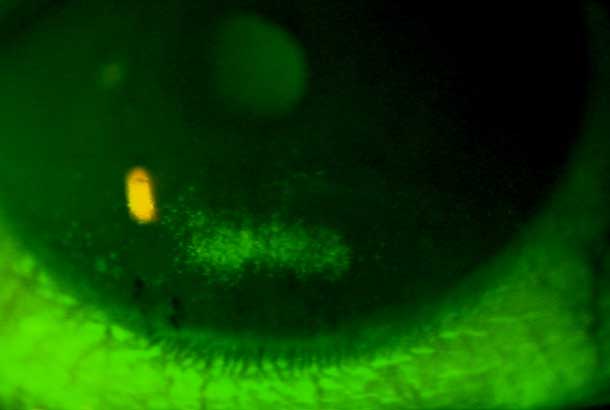

"detail": "<p>Staining</p>\n\n<h2>Symptoms</h2>\n\n<ul>\n\t<li>None to mild irritation</li>\n\t<li>May disturb vision if on visual axis</li>\n</ul>\n\n<h2>Signs</h2>\n\n<ul>\n\t<li>Indentations display un-reversed illumination with white light illumination</li>\n\t<li>Multiple, focal areas of sodium fluorescein pooling</li>\n</ul>\n\n<h2>Etiology</h2>\n\n<ul>\n\t<li>Indentations of epithelium resulting from air bubbles (rigid lenses) or mucin balls (soft lenses) trapped under lenses</li>\n\t<li>Most frequently seen with ill-fitting GP lenses (air bubbles) or SiHy lenses (mucin balls)</li>\n\t<li>In GPs, observed centrally with excessive pooling and peripherally with excessive edge lift</li>\n</ul>\n\n<h2>Prevalence</h2>\n\n<ul>\n\t<li>Occasional</li>\n</ul>\n\n<h2>Differential Diagnosis</h2>\n\n<ul>\n\t<li>See: <a href=\"/condition/65\">Epithelial Fluorescein Staining &ndash; Differential</a></li>\n</ul>\n\n<h2>Management</h2>\n\n<ul>\n\t<li>Refit GP lens with closer alignment to corneal shape</li>\n\t<li>Flatter BOZR, smaller TD, change to toric back surface</li>\n\t<li>Lens lubricants with EW SiHy, choose a lens with lower modulus</li>\n</ul>",